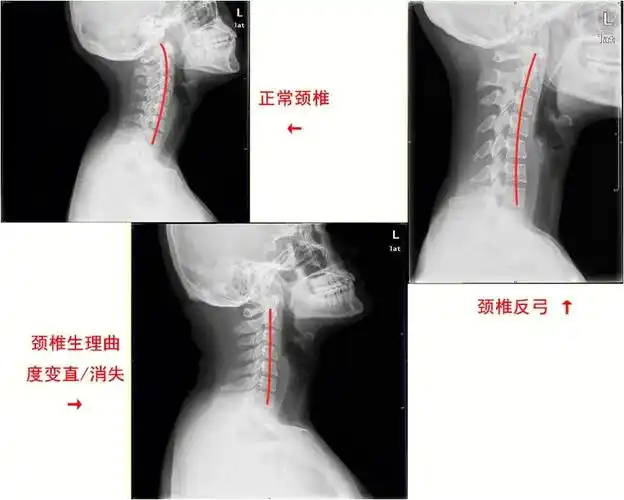

颈曲变直拿什么拯救你我的颈椎

碎片时间利用丨打造完美的脖颈曲线